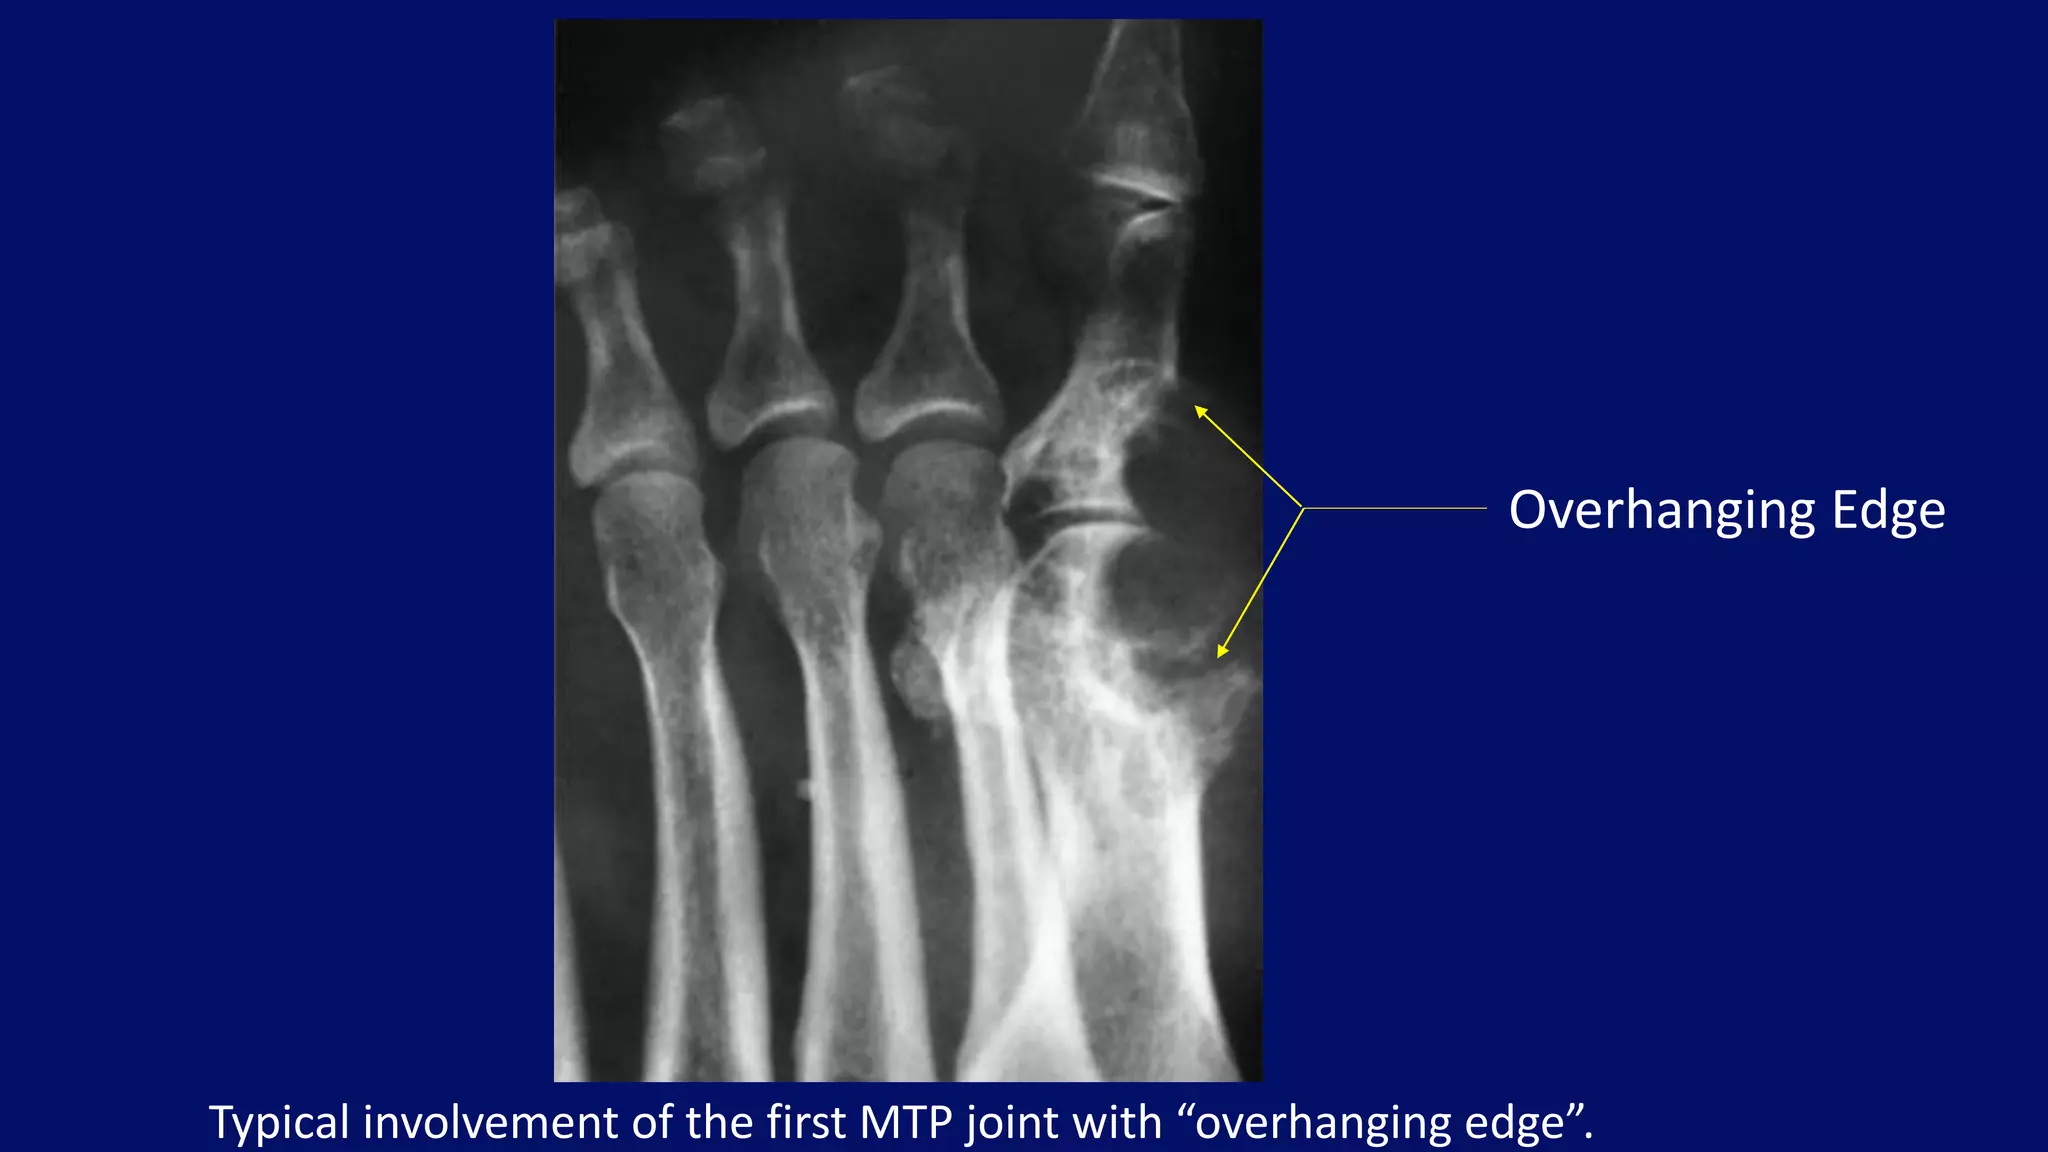

Typical involvement of the first MTP joint with “overhanging edge”.

Overhanging Edge

• #126 Oblique radiograph of the right foot of a 58-year-old man with a 3-month history of gout shows the typical involvement of the first metatarsophalangeal joint. Note the characteristic “overhanging edge” of the erosive changes and preservation of the lateral portion of the joint.